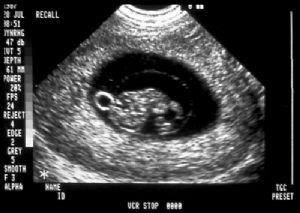

Normal nuchal translucency (NT) picture. Note calipers

on interior edge to interior edge of nuchal thickness.

4. Nuchal Thickness (NT)

1. How Done

• Combine in nomogram with maternal serum analytes, maternal age, and gestational age to calculate risk

• Use ultrasound nuchal thickness at 10 6/7 weeks to 13 6/7 weeks (<3mm is normal)